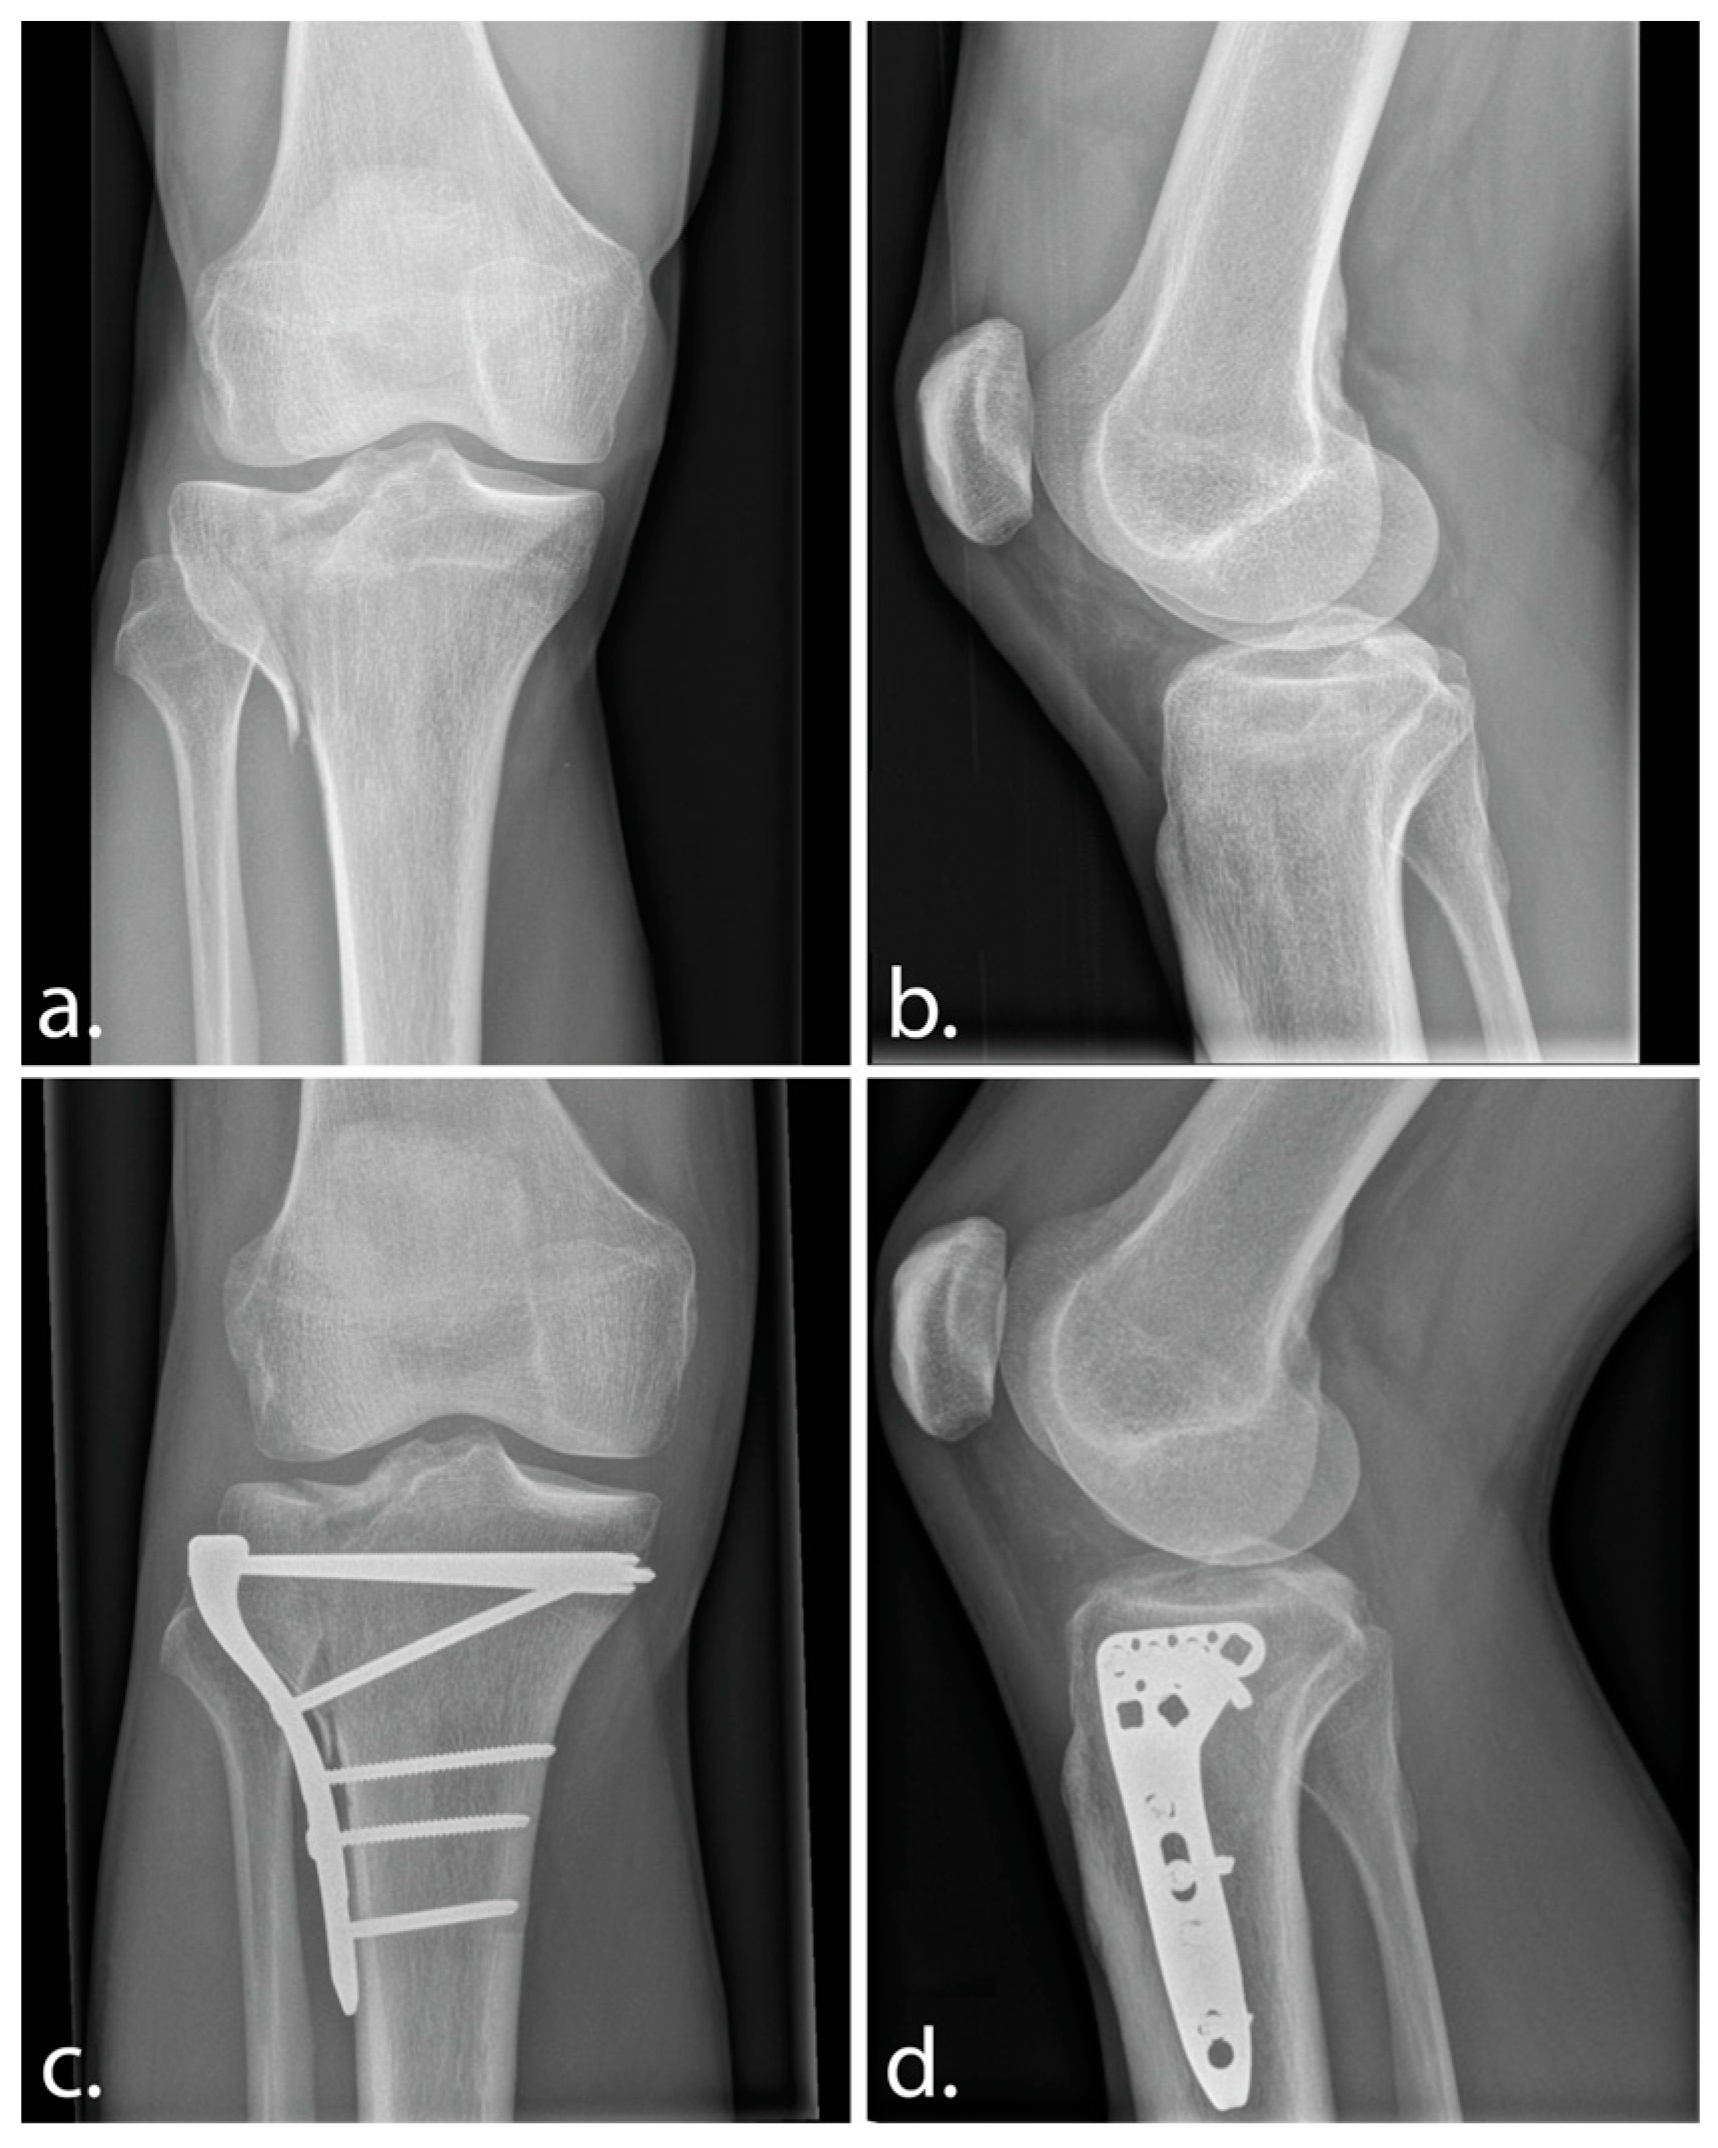

A 33-year-old male patient, working as a personal trainer, was referred to our outpatient clinic with an intra-articular malunion one year after index surgical treatment of a lateral split-depression tibial plateau fracture (Schatzker 2; AO 41-B3) (Figure 1a,b). Patient presented knee instability, subjectively reported when weightbearing in flexion (squats, stairs, hiking), and resulting pain. Patient reported no instability in full extension while standing and showed very good quadriceps recovery after index procedure.

Physical examination showed lateral defect laxity beyond 30 degrees of knee flexion, with the medial collateral ligament complex intact. Patient identified resulting pain upon examination, which was recognized as the pain during his example of squatting. Plain radiographs of the affected knee suggested slight widening and distal translation of the split fragment and of a defect at the site of traumatic depression of the lateral tibial plateau (Figure 1c,d). It was felt that the malunited split fragment, with widening and distal translation, allowed for the lateral femoral condyle to sink in the bony defect and was explanatory for the patient’s complaints; it was theorized that the femur fell into the defect beyond 30 degrees of flexion.

Figure 1. Anteroposterior and lateral radiograph of the initial tibial plateau fracture (a,b) and of the situation 1-year postoperative (c,d).